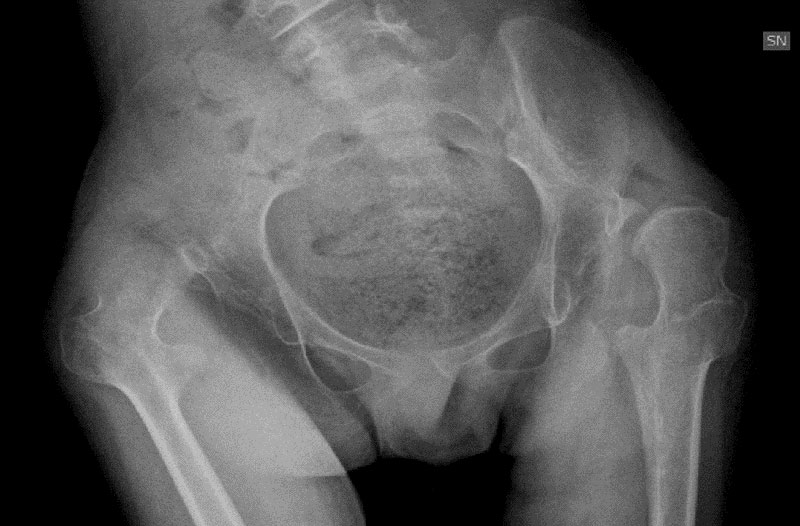

- resection of the femoral head, which is performed in the most serious cases of deformity of the femoral head and the acetabulum

- The pan release of all muscles of the thight that is performed in the most severe cases where the femoral head is completely deformed and the hip joint can no longer be reconstructed.